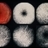

- 22-year-old white female. Fundus albipunctatus. 20/25- and 20/200.